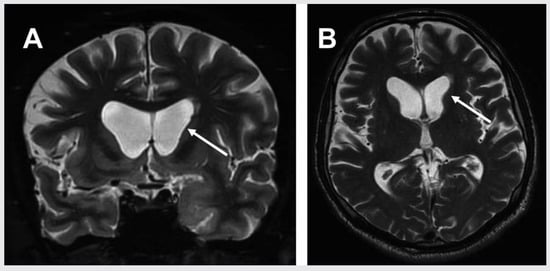

Could transient global amnesia be an epileptic phenomenon?

by Daniel Eschle and H.-G. Wieser

This mini-review entertains the concept that transient global amnesia (TGA) could possibly be part of the spectrum of transient epileptic amnesia (TEA), which is considered the most important differential diagnosis by many clinicians. To support this hypothesis we analysed EEG data, where conventional [...] Read more.

This mini-review entertains the concept that transient global amnesia (TGA) could possibly be part of the spectrum of transient epileptic amnesia (TEA), which is considered the most important differential diagnosis by many clinicians. To support this hypothesis we analysed EEG data, where conventional scalp recording was unrevealing, but nasopharyngeal electrodes demonstrated epileptic discharges in the medial temporal lobe, the region implicated in memory dysfunction during transient global amnesia. Full article